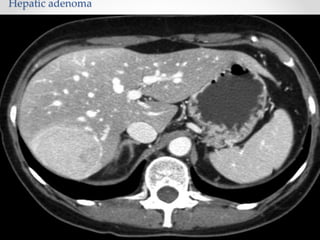

Adenoma

• Hepatic adenomas are benign solid neoplasms of the liver.

They are most commonly seen in premenopausal women older

than 30 years of age and are typically solitary.

• Use of Estrogen Contraceptives are clear risk factors.

• Histologically : Adenoma lacks bile duct glands , kupffer cells ,

have no lobules and contain hepatocytes that are congested.

• Hepatic adenomas also have a risk of malignant transformation

to a well-differentiated HCC. Therefore, it usually is

recommended that a hepatic adenoma (once diagnosed) be

surgically resected.

Hepatic adenoma